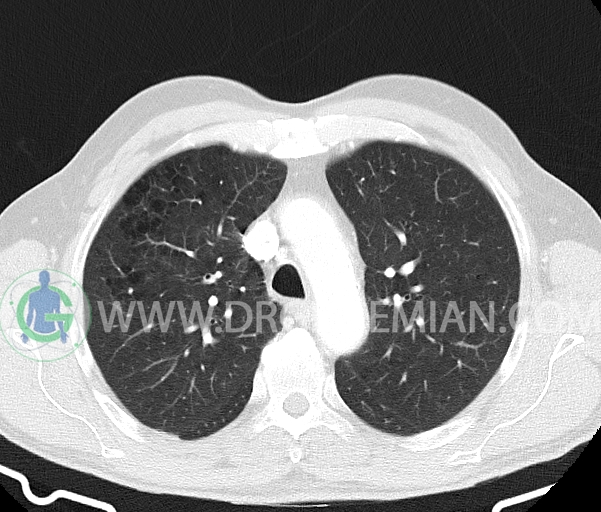

در سی تی اسکن اسپیرال ریه و مدیاستن- شکم و لگن با و بدون کنتراست خوراکی و وریدی (مولتی دیدکتور 16 با مقاطع ظریف و بازسازی های ساژیتال و کرونال) :

– آمفیزم سنتری لوبولار در لوب فوقانی هر دو سمت با ارجحیت در سمت راست

–آمفیزم پاراسپتال در هر دو ریه

–ندول Solid با حدود صاف به سایز 6x5mm (متوسط 6mm) در سگمان پوستریور بازال لوب تحتانی راست (تطبیق با مدارک قبلی )

– ندول پری فیشرال به سایز 6mm در فیشر مینور راست (بدون اهمیت بالینی )

–چند لنف نود در مدیاستن میانی و قدامی به حداکثر SAD=8mm در پره کارینا (بدون اهمیت بالینی)

–دو لنف نود در هیلوم ریه راست به حداکثر SAD=8mm